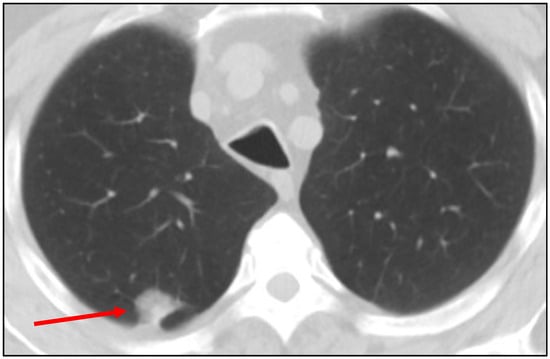

Background: Coccidioidomycosis is an endemic fungal infection in the southwestern United States that can present as solitary lung nodules, mimicking malignancy on imaging. Molecular testing, such as PCR, offers rapid diagnosis but its performance in this clinical setting remains unclear. Methods: We conducted a retrospective analysis of patients evaluated for lung nodules at a tertiary care community-based lung nodule clinic in Central California between 2011 and 2025. Coccidioides PCR in patients with proven or probable Coccidioidomycosis was compared to those with biopsy-proven lung cancer. Diagnostic yield of Coccidioides PCR was assessed across biopsy methods and benchmarked against histology and fungal cultures. Results: Among 122 patients with Coccidioidomycosis, PCR demonstrated low sensitivity (range: 20–41%) but high specificity (100%) across all biopsy modalities. Histology and fungal cultures outperformed PCR, detecting additional cases missed by molecular testing. Notably, 9 PCR-negative cases were confirmed on histology, and PCR was only positive in 71.4% of culture-confirmed cases. Conclusion: Coccidioides PCR testing has high specificity but limited sensitivity for diagnosing lung nodules in endemic regions, limiting its utility as a single test. Histology and fungal culture remain essential. Selective use of PCR may enhance diagnostic efficiency and reduce unnecessary costs in regions burdened by Coccidioidomycosis.

Figure 1